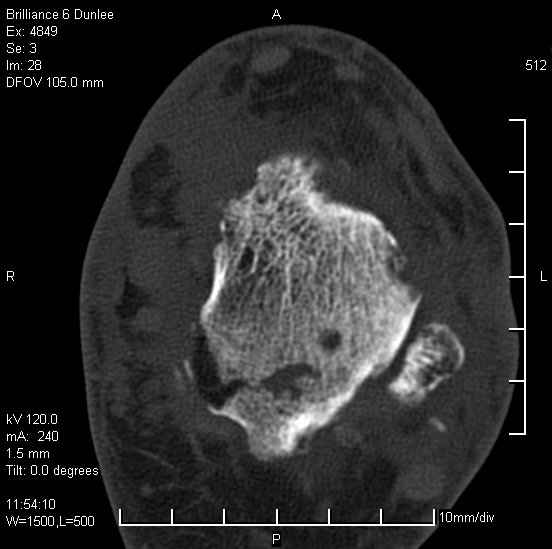

На лечении находится пациент 35 лет. Травма в сентябре 2008 г.- открытый вывих таранной кости

В день травмы ПХО, вправление вывиха, трансартикулярная фиксация. Рана зажила первично. С января нагрузка на конечность. С конца апреля- болевой синдром. На рентгенограммах и КТ признаки ас. некроза таранной кости, артроз подтаранного и голеностопного суставов.